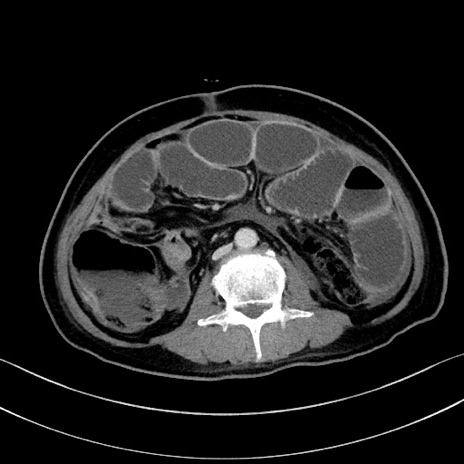

症例28(横断像)

【症例】60歳代男性

【主訴】嘔吐

【現病歴】胃癌にて胃全摘後。食思不振が悪化し、夜中に嘔吐することがある。

【既往歴】胃癌、胃全摘、脾摘、胆摘後

【データ】WBC 5900、CRP 10.56